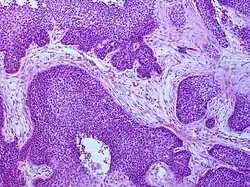

_squamous_cell_carcinoma_histopathology.jpg)

Medical history, physical examination and medical imaging may suggest a squamous-cell carcinoma, but a biopsy for histopathology generally establishes the diagnosis. TP63 staining is the main histological marker for squamous-cell carcinoma. In addition, TP63 is an essential transcription factor to establish the identity of the squamous cells.[18]